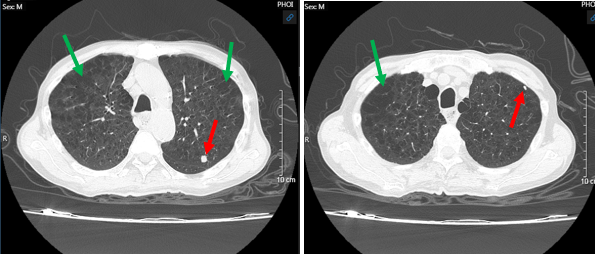

- Hình ảnh chụp cắt lớp vi tính ngực – bụng (15/03/2024):

Hình 1: Hình ảnh chụp cắt lớp vi tính ngực – bụng: U vùng rốn phổi phải (mũi tên đỏ) xâm lấn tâm nhĩ trái (mũi tên xanh) nghi ngờ huyết khối buồng nhĩ trái và u thùy dưới phổi phải (mũi tên màu vàng cam).

Hình 3: Hình ảnh chụp cắt lớp vi tính ngực – bụng: U phổi bên trái - Theo dõi tổn thương di căn (mũi tên đỏ), giãn phế nang 2 bên phổi (mũi tên xanh).

Hình 4: Hình ảnh chụp cắt lớp vi tính ngực – bụng: Hạch trung thất nhóm 7 (mũi tên xanh), u chèn ép thực quản gây ứ đọng dịch, thức ăn (mũi tên đỏ).

Kết luận: Hình ảnh khối u vị trí rốn phổi phải và thùy dưới phổi phải, xâm lấn nhĩ trái gây huyết khối buồng nhĩ trái, xâm lấn thực quản, cơ hoành, nhu mô gan phải. Nốt đặc rải rác phổi trái, hạch trung thất, nốt tuyến thượng thận trái – theo dõi tổn thương thứ phát. Giãn phế nang rải rác nhu mô phổi 2 bên.